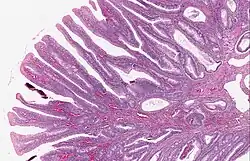

| Villous adenoma | 15%[16] to 40%[15] | Over 75% villous[14] |

| |

The villous subdivision is associated with the highest malignant potential because they generally have the largest surface area. (This is because the villi are projections into the lumen and hence have a bigger surface area.) However, villous adenomas are no more likely than tubular or tubulovillous adenomas to become cancerous if their sizes are all the same.[18]

Micrograph of a villous adenoma. These polyps are considered to have a high risk of malignant transformation. H&E stain. -